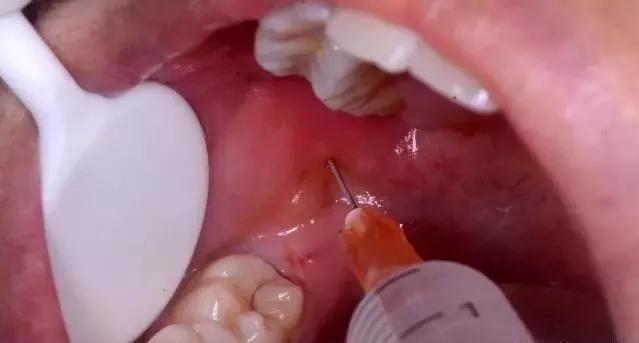

正常情况下打麻药一支后,牙龈部分开始麻木,随着药效逐渐扩散,在2小时内拔牙过程舒服,几乎没有痛感,不过有些患牙拔除难度大,拔除时间较长,可能到后面药效不明显,得考虑打第二支麻药。

1、像这种拔牙小剂量就能麻醉完成手术,要是超过一定量的话,拔牙麻木效果明显,智力方面倒没事,但术后整个口腔会长时间没有知觉,危害到牙神经,要等过几天才会恢复,当然也得看注射的是什么药物。